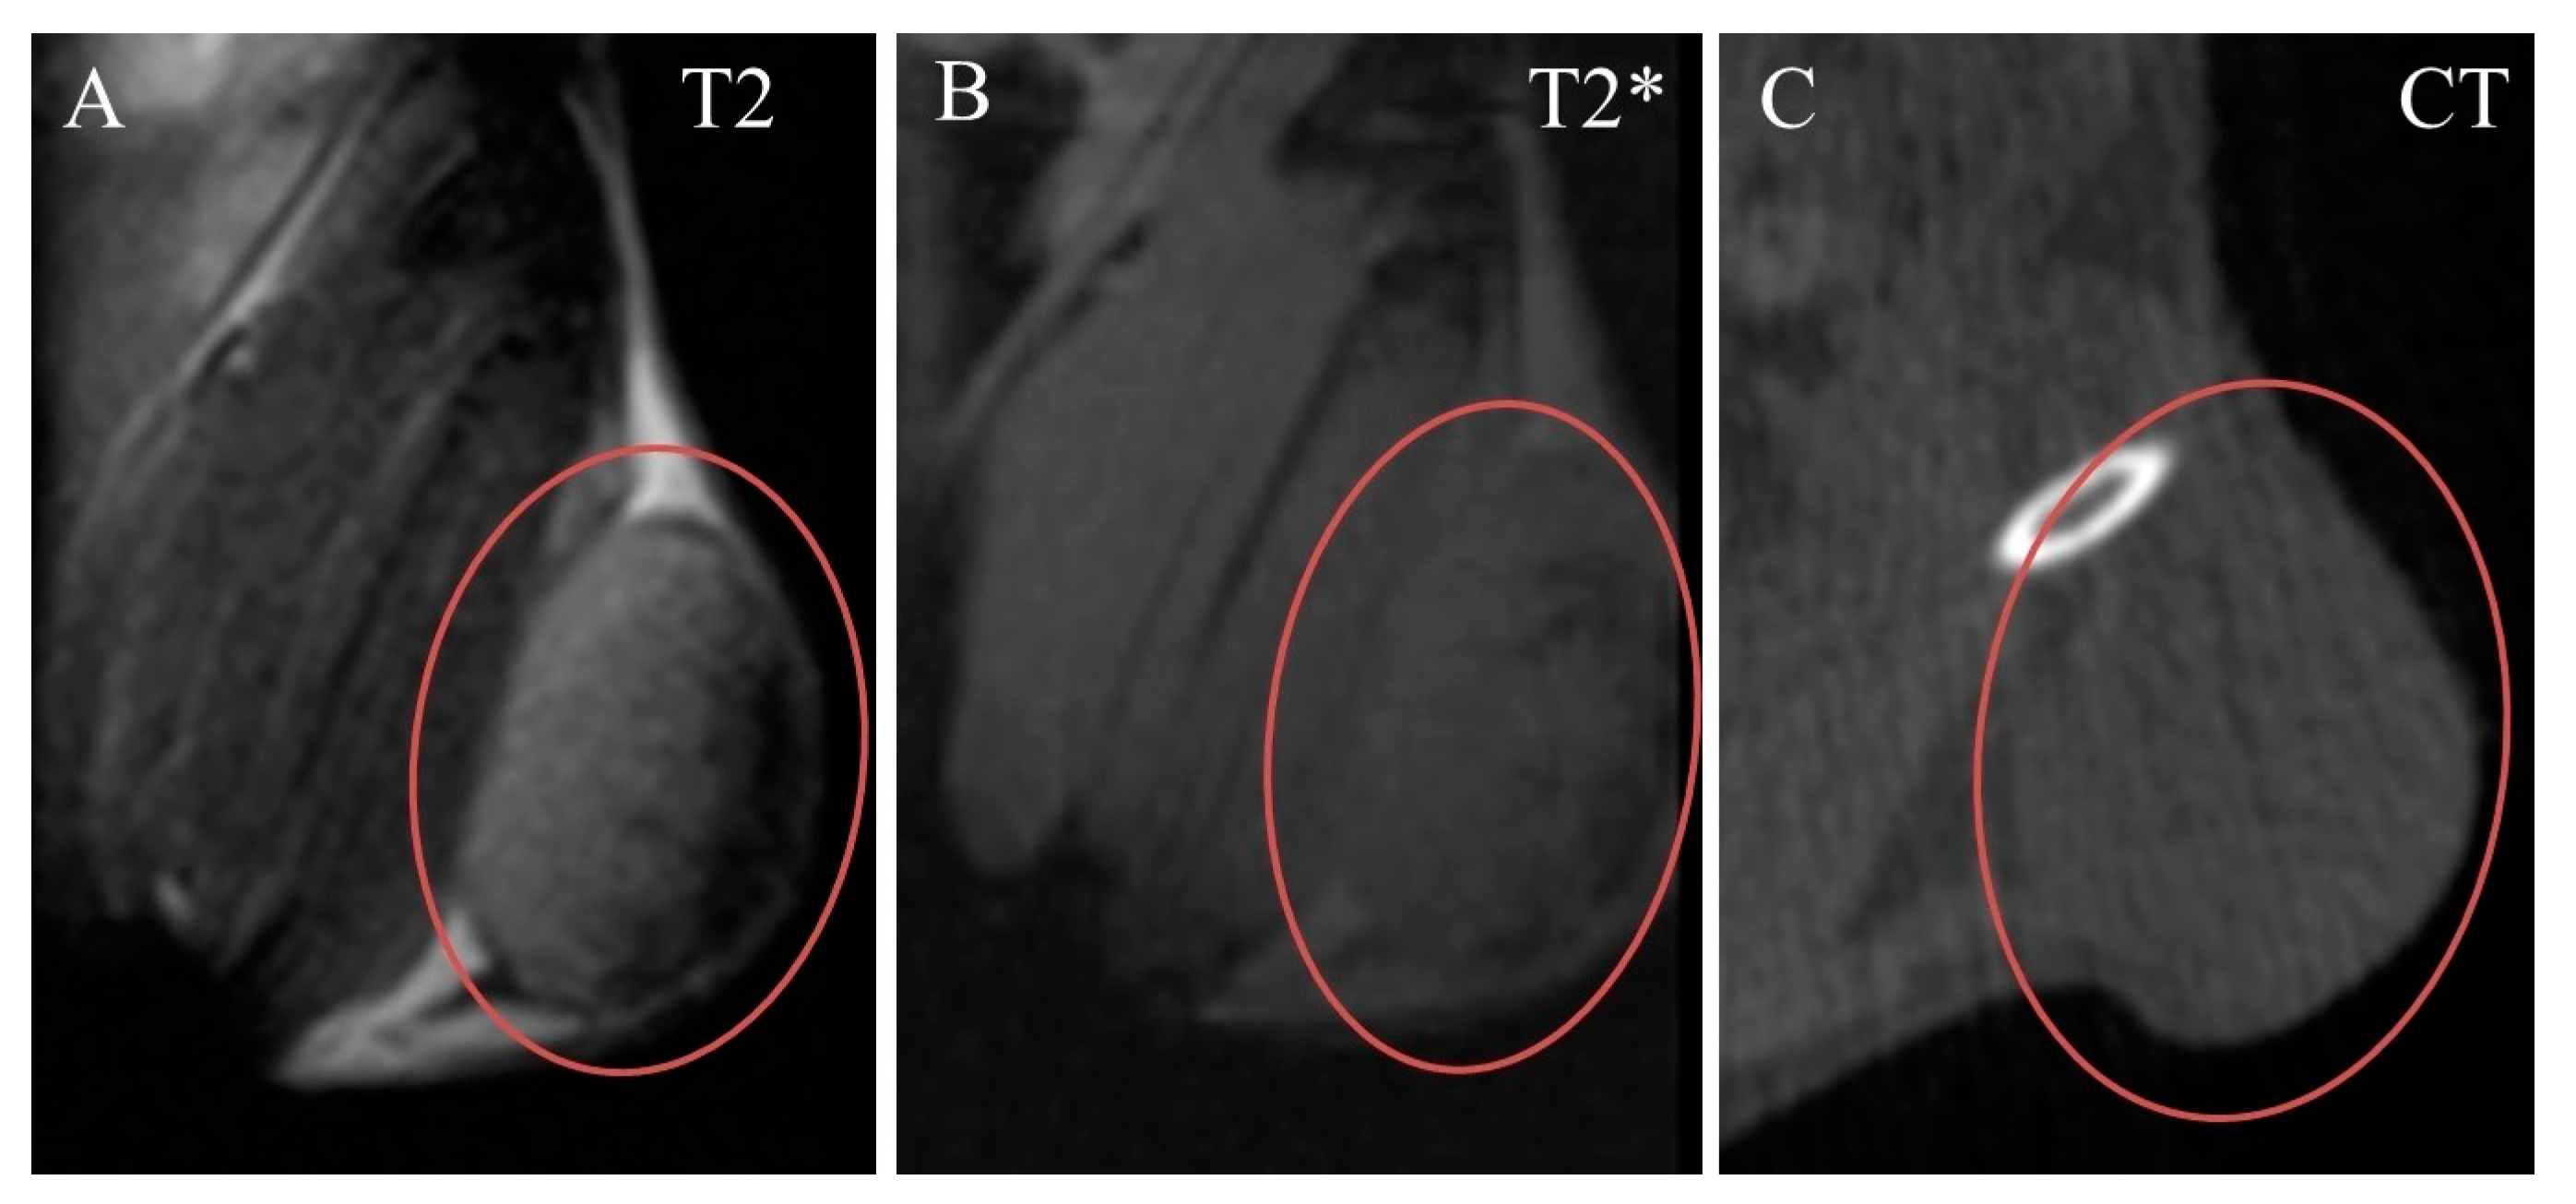

The tumor was clearly seen in CT and MRI. It was nearly ellipse-shaped and approximately 7 × 7 × 5 mm in size. Native images of the tumor were slightly hyperintense in T2-weighted, and nearly isointense in T2*-weighted MRI, compared to adjacent muscle (Figure 4A,B). Its structure was nearly homogenous, with a small subcapsular T2-hypointense portion (Figure 4A). In CT, the tumor was isodense to muscle and completely homogenous (Figure 4C).

Figure 4.

Native coronal images of Ca755 mammary carcinoma. (A) T2 MRI; (B) T2* MRI; (C) CT image. The tumor is located on the right hind leg.